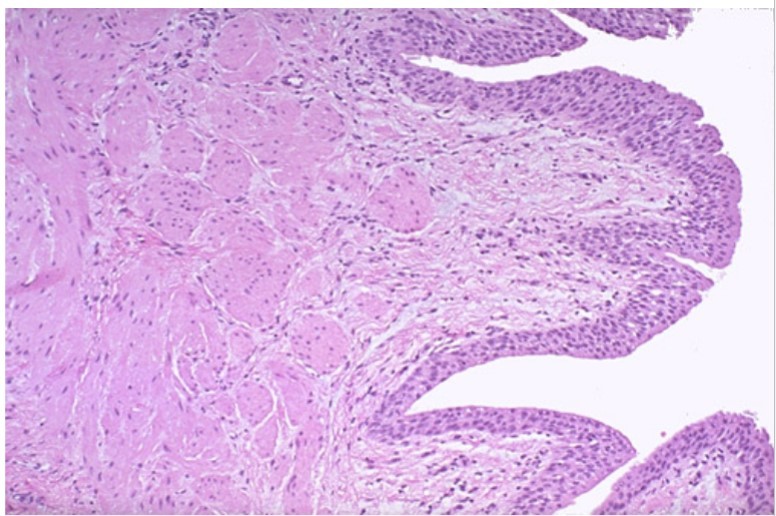

Ureter (histo)

Ureter mucosa (histo)